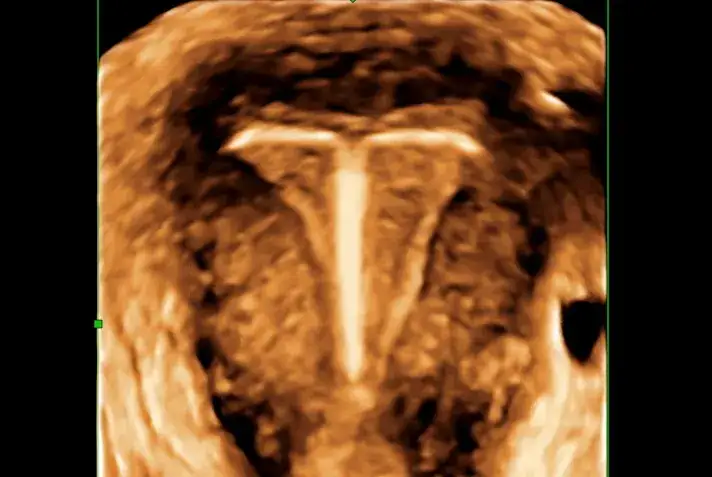

Zobacz, jakie są objawy przesunięcia wkładki domacicznej. Dowiedz się, kiedy należy skontaktować się z lekarzem i jak dbać o zdrowie reprodukcyjne.